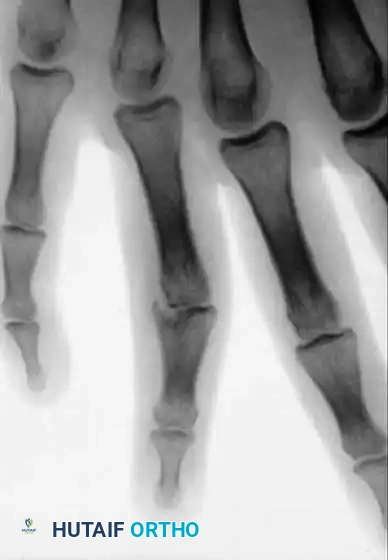

COMPLICATIONS OF HAND FRACTURES Surgical Diagram

Management of Articular and Condylar Malunions

Certain malunions involving the articular surface require meticulous intra-articular osteotomies or grafting. When articular cartilage loss results in angular deformity, subluxation, dislocation, impending joint destruction, or intractable pain, osteoarticular grafts may be highly useful.

Fig. 64-68 A, Displaced, unstable condylar fracture usually requires open reduction and fixation. B, Manipulation of fracture using intact collateral ligament may permit insertion of Kirschner wire to hold reduction. C, Two wires may be necessary to avoid rotation of reduced fragment.

Fig. 64-67 A and B, Condylar fracture fixed with Kirschner wires.